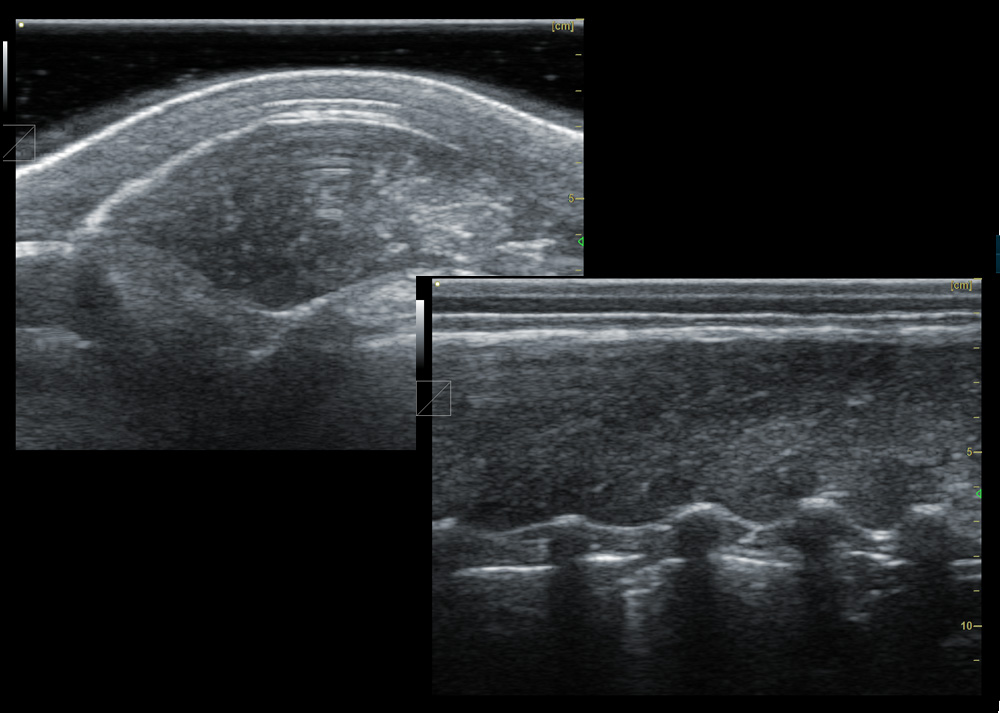

2. Animal back fat eye muscle probe:

2.1. Frequency: 2.5-6MHz 18cm long linear array probe

2.4, Probe scanning depth can reach 30cm

IV. Features of animal backfat eye muscle probe:

1. 18cm long professionally designed backfat eye muscle probe, which can fully test the backfat eye muscles of various animals

2. The probe scanning depth can reach 30cm, which can well present the eye muscles of large animals

3. High-frequency probe and high-quality Doppler color ultrasound images can well identify the measured muscle quality grade